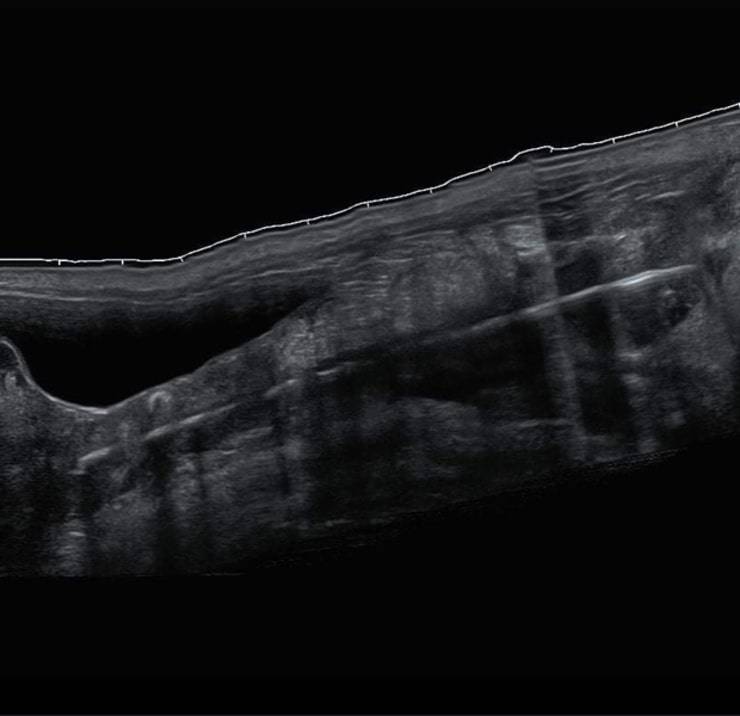

Così il veterinario sospettando un’ostruzione indirizzò Richard Davidson verso l’Abington Park Veterinary Surgery di Northampton dove un team specializzato, dopo diverse ecografie riuscì finalmente ad individuare il vero problema.

Il piccolo infatti continuava a mangiare e bere normalmente, a destare grande preoccupazione era solo la sua zampa che continuava ad essere gonfia. Il che ha portato i veterinari ad osservare più attentamente l’arto, accorgendosi che proprio vicino ai grandi vasi addominali e all’arteria femorale vi era il bastoncino appuntito.

Uno dei veterinari ha infatti asserito: “Non appena è entrato Bear e ho fatto un’ecografia ho potuto vedere il corpo estraneo”

“Anche se la gamba era enormemente gonfia, mi aspettavo qualcosa come un seme d’erba, non qualcosa di grande come il bastoncino di uno spiedino”.

“Non c’erano ferite o punti di ingresso, quindi era difficile immaginare come fosse entrata qualcosa del genere”.

“L’immagine ha mostrato che era molto vicino ai grandi vasi addominali e all’arteria femorale. Mi sono reso conto che era necessario un intervento chirurgico perché c’era il rischio di emorragia se avessimo tentato di rimuoverlo in modo non invasivo “.